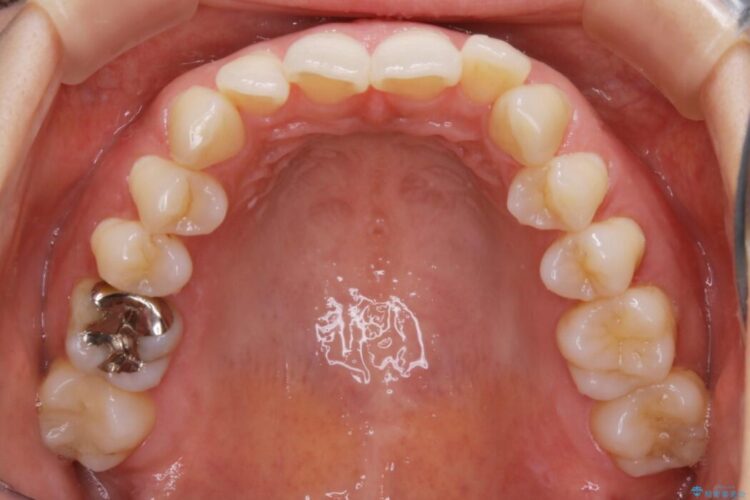

検査したところ歯の叢生自体は歯列幅の拡大やディスキング(IPR)で解決できる範囲内でした。

ですが、上顎左側の歯が前方へ寄っている状態であるため噛み合わせにズレが生じていました。